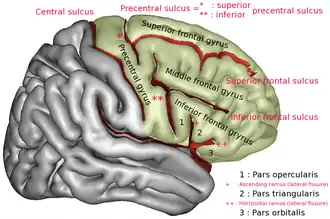

The precentral gyrus is a prominent gyrus on the surface of the posterior frontal lobe of the brain. It is the site of the primary motor cortex that in humans is cytoarchitecturally defined as Brodmann area 4.

The precentral gyrus lies in front of the postcentral gyrus - mostly on the lateral (convex) side of each cerebral hemisphere - from which it is separated by the central sulcus. Its anterior border is represented by the precentral sulcus, while inferiorly it borders to the lateral sulcus (Sylvian fissure). Medially, it is contiguous with the paracentral lobule.